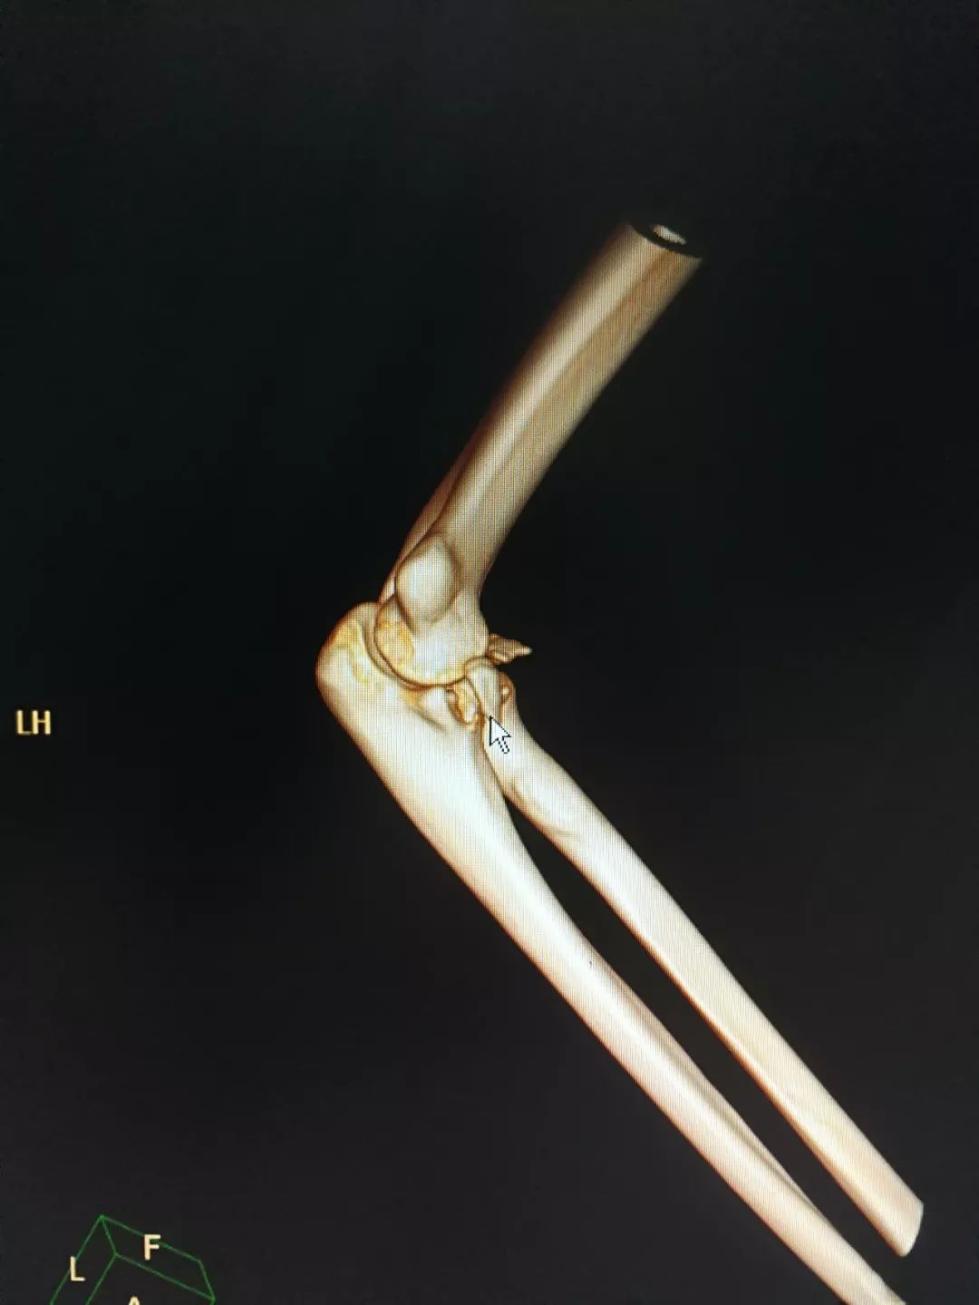

20日中午,20歲的年輕小伙李帥(化名)托著右手走進武漢市第四醫(yī)院骨科急診室,醫(yī)生黃振峰一眼就看到李帥右手肘嚴重畸形,初步判斷李帥的手臂應該發(fā)生了骨折。經(jīng)過進一步CT檢查,果然發(fā)現(xiàn)患者右手肘骨折伴脫位。

目前,患者傷情比較嚴重,除了骨折,韌帶也受傷了,在進行復位后,后期還需要接受手術治療。

黃振峰介紹,曾接診過因“公主抱”致腰部受傷的患者,但是發(fā)生手臂骨折的情況較為少見。除了體能問題,可能也與李帥當時的姿勢有關。